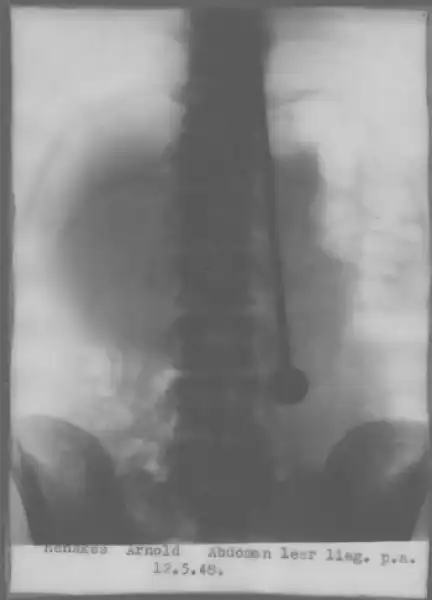

Конечно, Дажо проверяли врачи, причем не раз. В конце мая 1947 года он продемонстрировал свои таланты в Цюрихском кантональном госпитале. Как обычно, Ми-рин разделся до талии. Когда ассистент пронзил рапирой сердце, легкие и почки, он, как обычно, не почувствовал боли и не проронил ни капли крови. Чтобы исключить возможность гипноза, было решено сделать рентген, но медики не знали, как доставить его до рентгеновского кабинета — ведь носилки не приспособлены к транспортировке людей, пронзенных рапирами. Дажо успокоил их, сказав, что сам дойдет куда нужно — с рапирой естественно. Снимки исключили всякие сомнения: клинок прошел через несколько жизненно важных органов,но не причинил никаких повреждений.